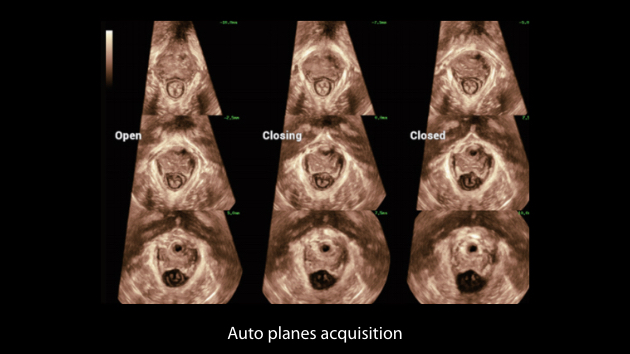

Obrazy kliniczne